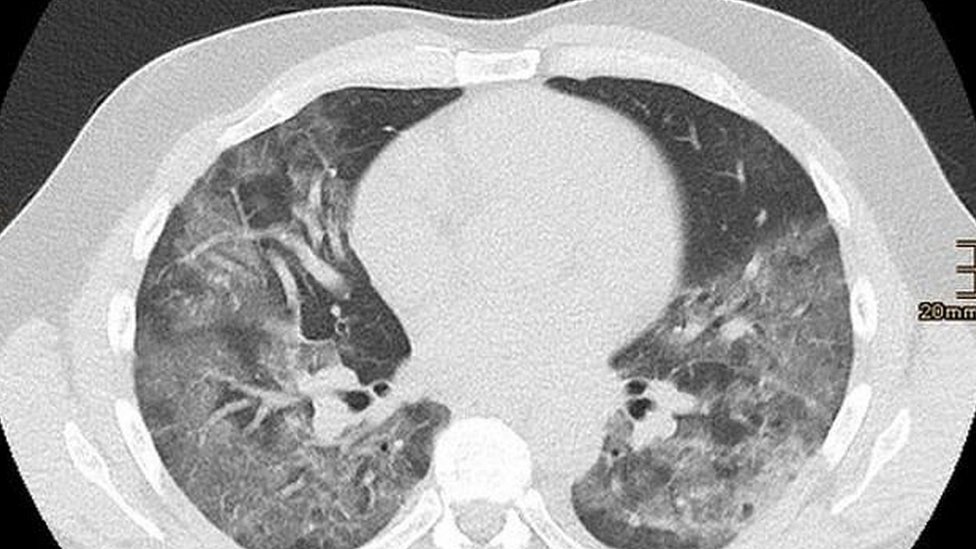

1.000.000 hingga lebih dari rp. 16.03.2020 · gambar ct scan dari seorang pria berusia 44 tahun yang mengalami demam selama 4 hari akibat virus corona. 25.07.2021 · dilansir dari webmd, sebanyak 80 persen pasien covid mengalami gejala ringan hingga sedang. Berapa biaya yang diperlukan untuk ct scan? Biasanya pasien bisa merasakan batuk kering dan sakit tenggorokan. Besaran biaya yang dibutuhkan untuk melakukan ct scan bervariasi tergantung dari rumah sakit, kelas perawatan, dan bagian tubuh yang akan diperiksa. Hasilnya, menunjukkan pola kelainan yang mirip dengan korban sars dan mers. Dalam masa perawatan kritisnya, chandra mengatakan disodorkan biaya obat dan perawatan sebesar rp 660 juta yang harus ditanda tangani agar proses pengobatan bisa berjalan.

Hasilnya, menunjukkan pola kelainan yang mirip dengan korban sars dan mers.